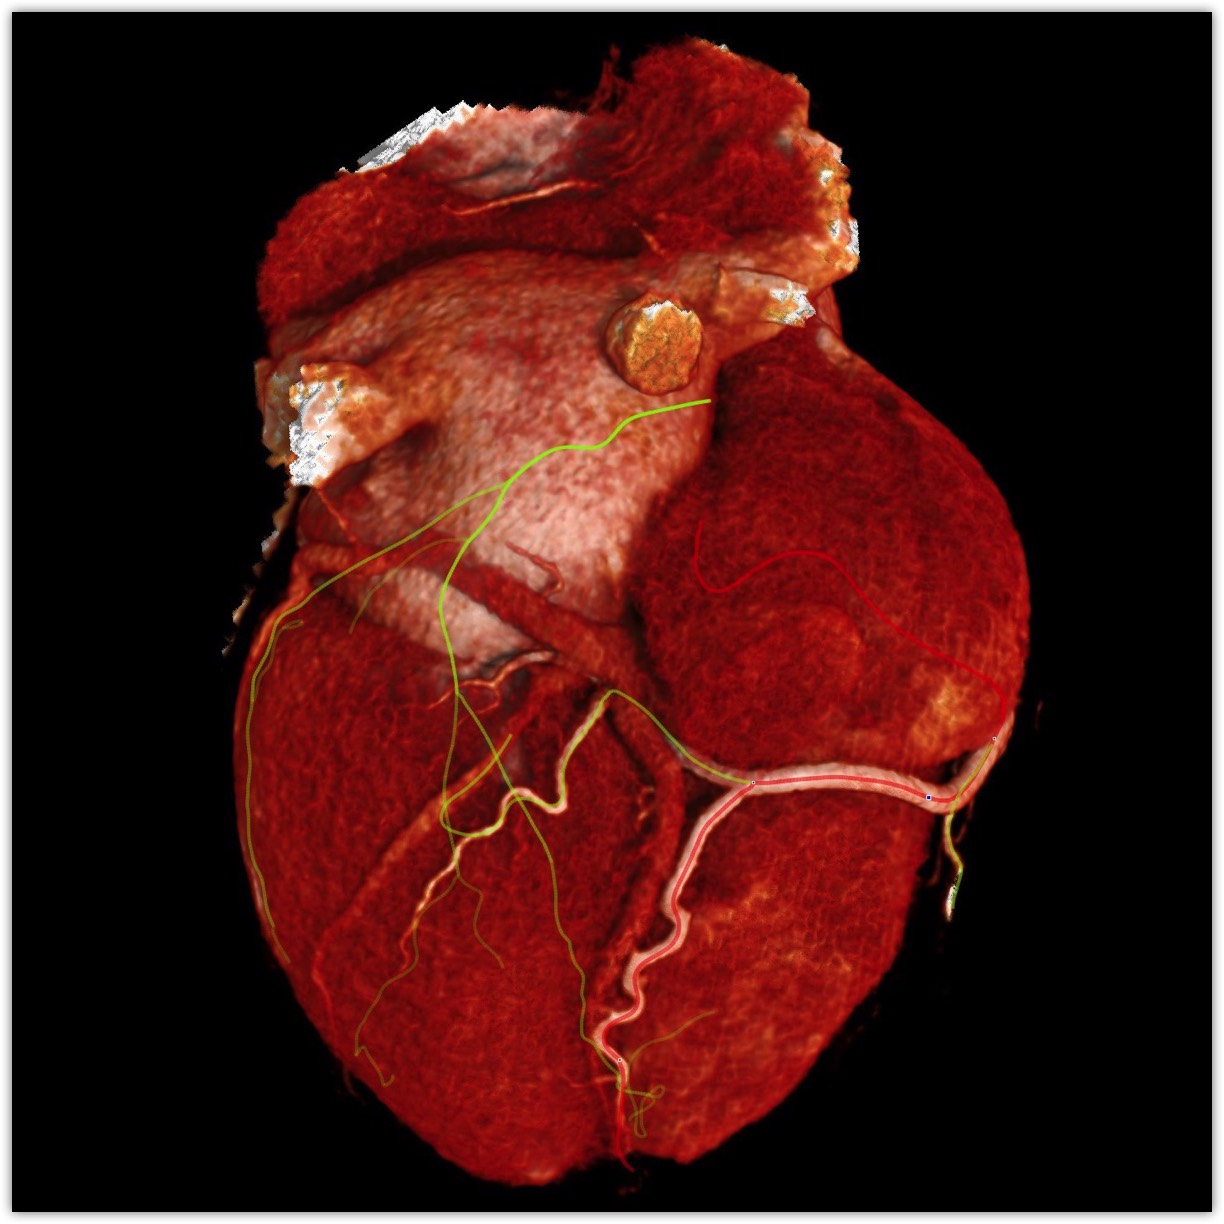

We believe in keeping you as healthy as possible. One of the ways we do this is by checking for heart disease with a Coronary CT Angiogram (CCTA) — a non-invasive scan that can see disease in your heart vessels even if you have no symptoms.

Most people have no symptoms until it’s too late. A Coronary CT Angiogram (CCTA) lets us see disease in the vessels of your heart — before a heart attack happens.

LAD scan